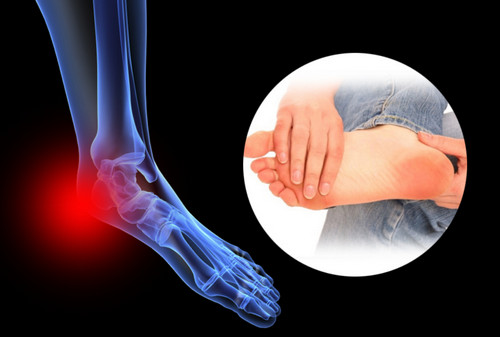

족저 근막염이란?

족저근막염이란 발바닥 뒤꿈치에 염증이 생기면서 나타나는 발바닥 통증을 일컫습니다. 이는 남성보다 여성이 2배 정도 많이 발병된다고 하는데, 그 원인은 과도한 발의 스트레스나 운동으로 인해 발병된다고 합니다. 이 밖에 몸무게의 급격한 증가나 평발도 발병 확률을 높이는 원인이 됩니다.

족저 근막염의 가장 흔한 증상으로는 아침에 통증이 매우 심하다는 점입니다. 그 이유는 밤사이에 족저근막이 수축되었다가 잠에서 깨서 일어나며 지면을 내딛는 순간 스트레칭 되면서 통증이 발생되기 때문입니다. 보통 원인은 종아리의 과단축으로 인하여 발바닥 근막이 당겨지면서 발병하는 경우가 대부분입니다. 때문에 족저 근막염을 예방하려면 평소 종아리와 발바닥을 같이 관리해 주어야 합니다. 만약 족저 근막염에 걸린 경우에는 생활 개선과 함께 필요에 따라 약물이나 의료적 치료가 병행되어야 합니다.